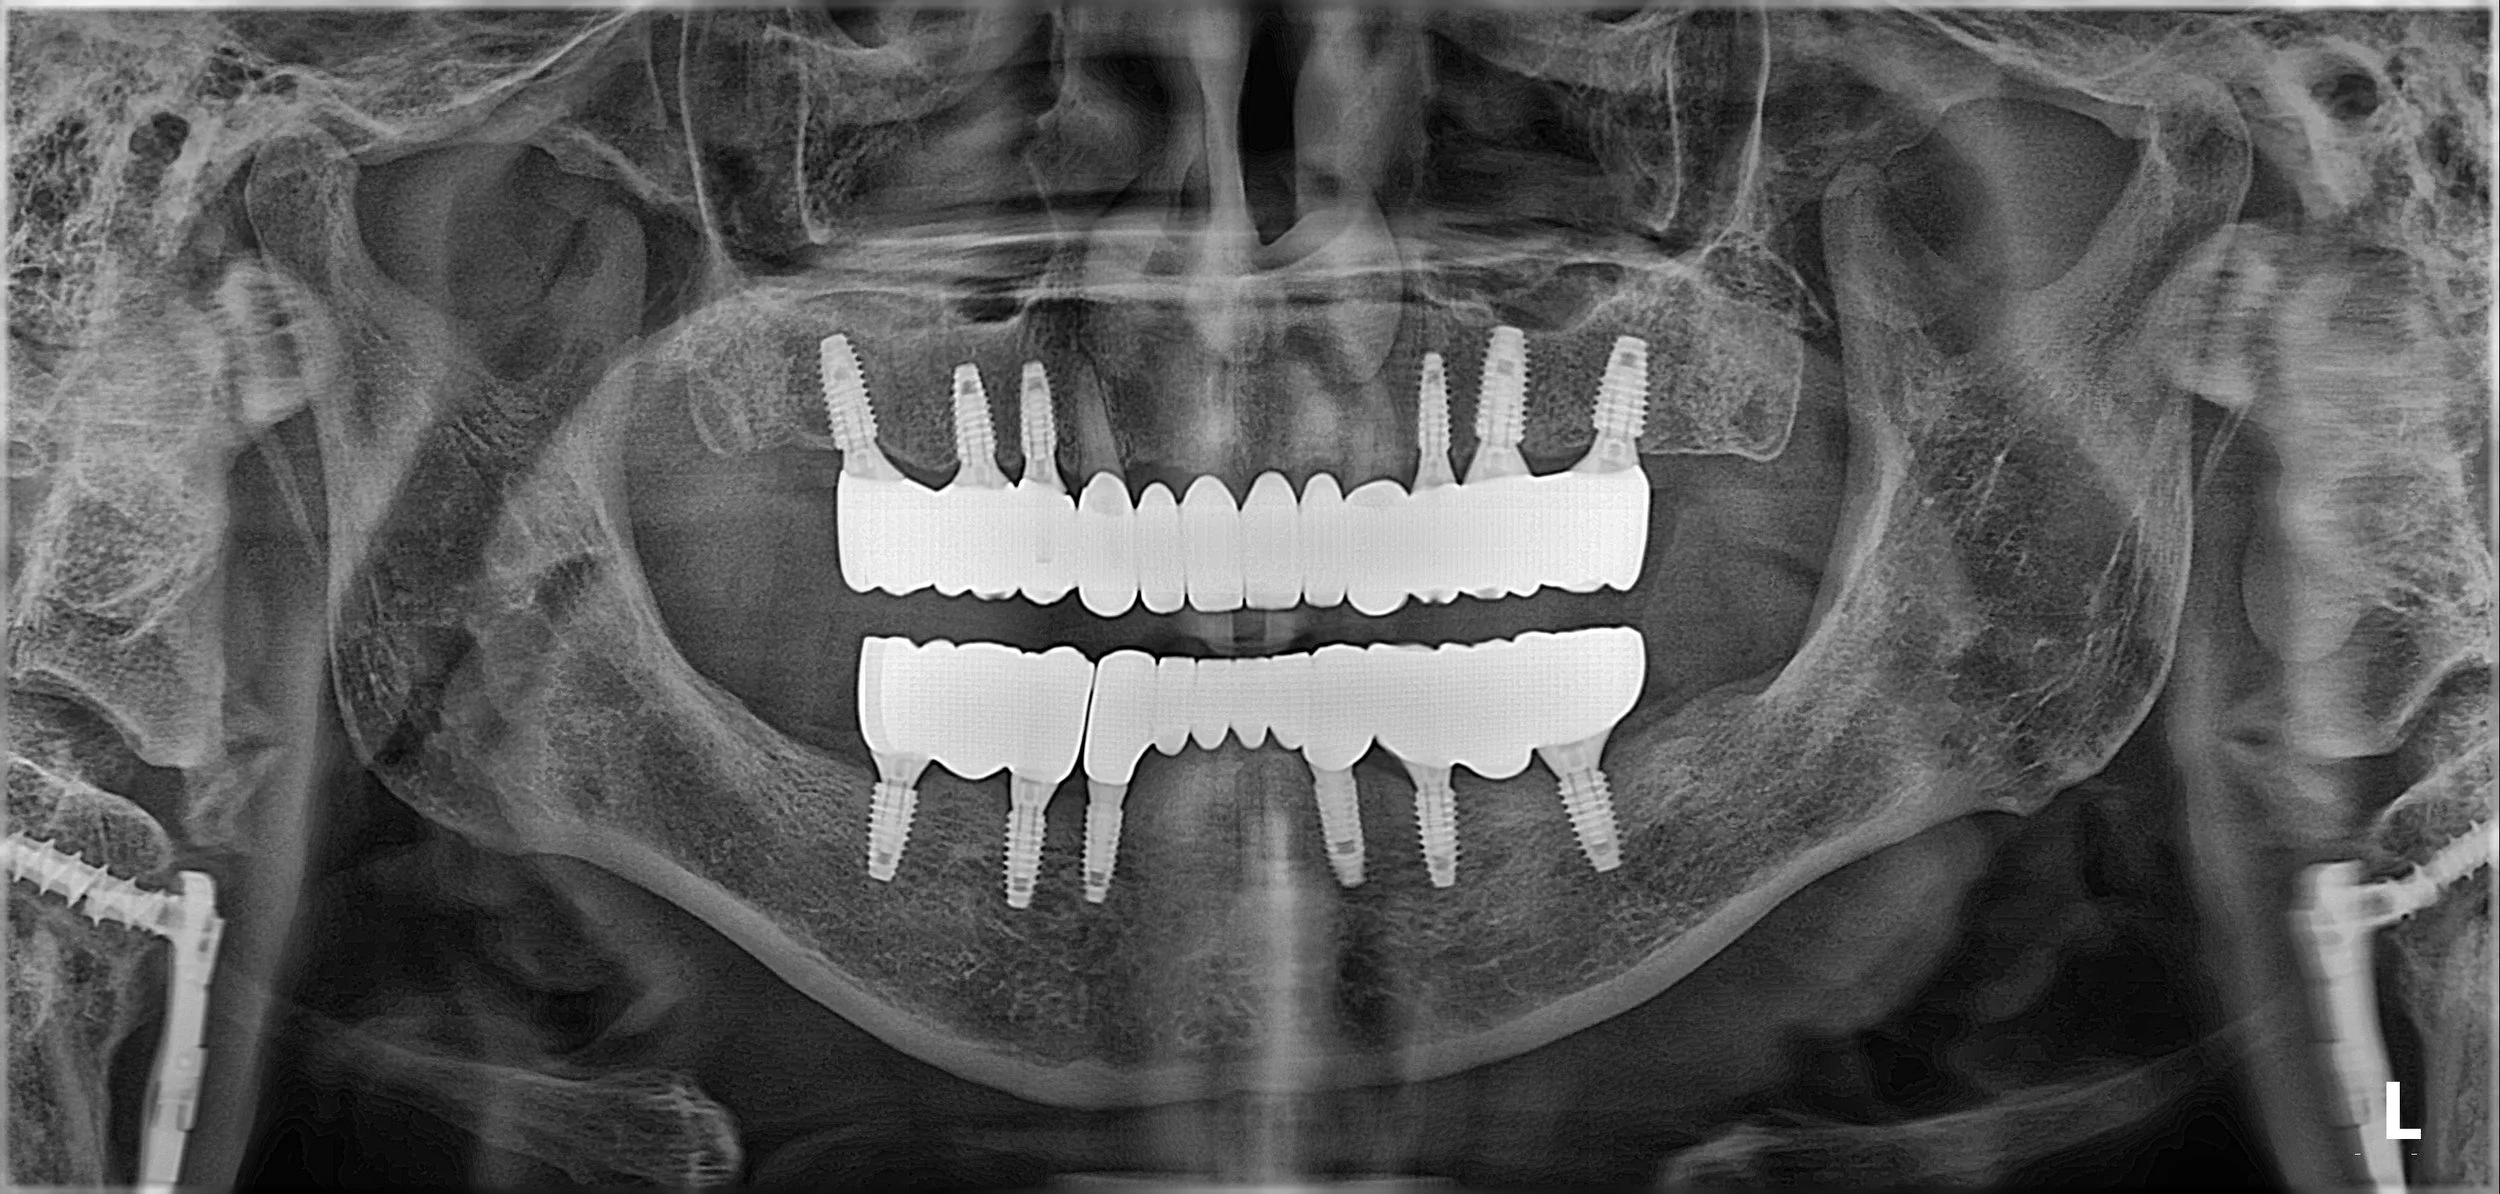

1. Foundation Phase: Dental implants were placed in the edentulous posterior regions. The goal was to create a "posterior stop" that would allow for a stable and repeatable bite.

3. Prosthetic Integration: The natural anterior teeth were restored and harmonized with the posterior implant-supported bridges. By integrating natural teeth with implants, we achieved a balance between surgical simplicity and biological preservation.

4. Final Delivery: Once the bite was verified as stable and the patient was fully adapted to the new occlusal scheme, the final high-strength zirconia restorations were delivered.